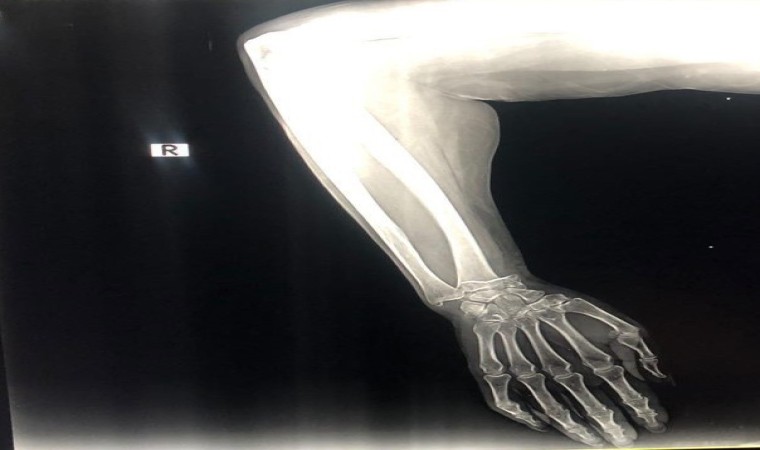

"Röntgen çekildi, cerrah kolu düzeltti ve bir alçı uyguladı"

"Cuma günü annemle çarşıya gittik. Sebzelerin yanında çok su vardı. Annem kaydı ve düştü. İnsanlar yardım etti, ambulans çağırdı. Ambulans geldiğinde sigorta olup olmadığını sordular. Ne yazık ki yoktu. Ukrayna’da bir savaş var. Şimdi yaşamak zor. Hangi hastaneye götürüldüğümüzü bilmiyordum. Orada doktorlar tıbbi bakım sağlamaya başladı. Ücretsiz olmadığını söylediler. Başka bir kliniğe gidelim dedim. Doktor ’Türkiye’nin her yerinde pahalı’ dedi. Röntgen çekildi. Cerrah kolu düzeltti ve bir alçı uyguladı. Bin 650 dolarlık bir fatura çıkardılar. Sonra acilen ameliyat gerektiğini söylediler."

Şeyhmus Doğan, “Hastaneye geldiklerinde sadece bir röntgen ve bu alçıyı yapıyorlar. Yatış yok, bıçak yok, ameliyat yok ve bin 650 dolar fiyat çıkıyor. Eşim devlet hastanesine gitmek istiyor, orası daha fazla para alır diyerek onu bu parayı ödemeye zorluyorlar. 44 bin 500 TL ödediler, 10 adet sargı bezi ve transfer. Ertesi gün ben gittim ve itiraz ettim. Polis çağırmamamı istediler. 850 dolarını geri yatırdılar. Kalan 800 dolar. Yine de bu alçıya 800 dolar verilir mi? Bu insanlar savaştan kaçtı, ben asgari ücretle çalışan birisiyim. Büyüklerimizin sesimizi duymasını istiyorum” diye konuştu.